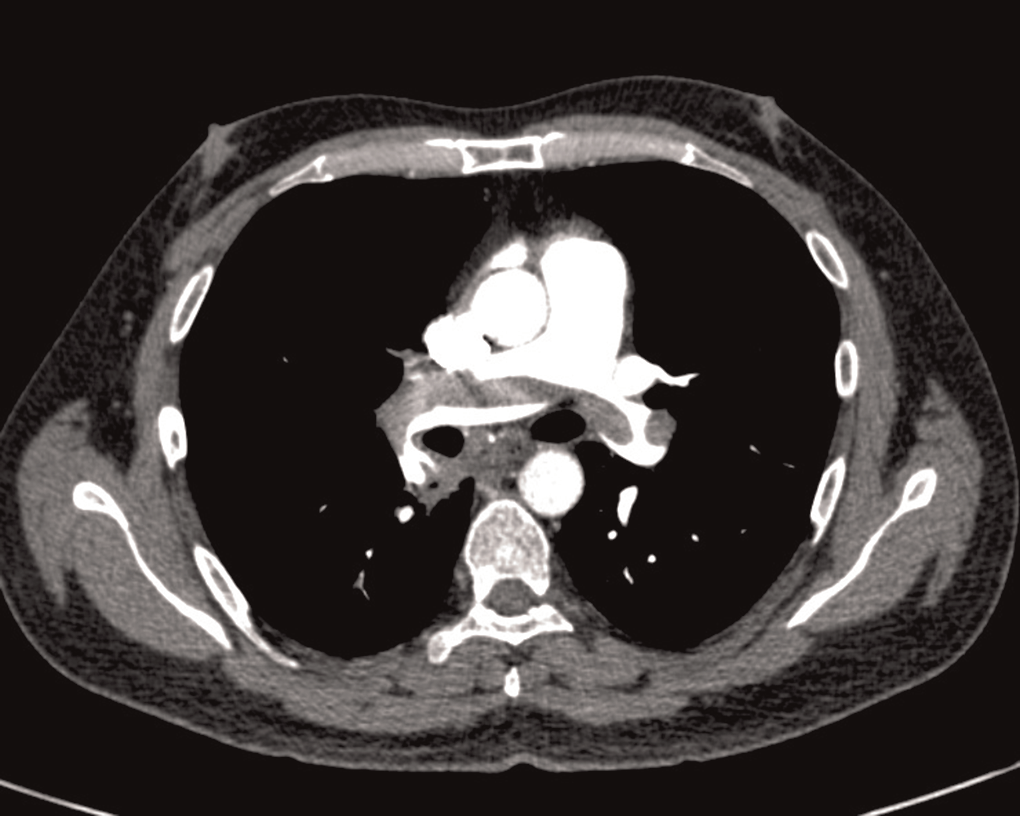

(BP 90/70). On cardiac system examination he had engorged neck vein. Other systems were found to be normal. He had normal CXR and ECG showed sinus tachycardia, S1Q3T3 with features of right ventricular hypertrophy and right axis deviation. Routine haematological parameters and coagulation profile were within normal limit (Hb 15.2 g/dL; TLC 8760/mm3; Platelet count 45,2000/mm3). Both d-dimer (2.69 mg/L) and cardiac troponin T was positive. Echocardiography at admission showed both RA and RV dilation with features of RV dysfunction and PASP of 72 mmHg. In this case CTPA was done in emergence which showed thrombi in both right and left pulmonary artery (Figure 1). Doppler venography was found to be normal. He was also give injection of STK for 48 hours with no complication. In this case also patient was incidentally diagnosed as having HIV infection. The PASP had come down to 42 and 30 mmHg at 24 hours and seventh day of treatment. Patient was discharged and referred to HIV centre after starting oral anticoagulant. This case belonged to WHO clinical stage I (asymptomatic) of HIV infection with CD4 count was 521 cell/mm3.

In the search of suspected pulmonary emboli, basic imaging investigations may support clinical suspicion and exclude alternative diagnoses. Chest radiographic appearances may be relatively non-specific and often confusing. CTPA is the imaging modality of first choice.4 One of our patients had CTPA features of PE but in another case CTPA was normal though it was done 24 hours after receiving injection STK. Though first case had significant weight loss but other case did not have any feature of HIV infection. Treatment of PE in cases with HIV also same as patient without HIV infection. As both the patients had features of RV dysfunction, so they were treated with injection of STK.8 We have treated both the cases with injection of STK and both the patients showed improvement with this treatment. Oral anticoagulant was also started. Some ART can have interaction with oral anticoagulant. 7 But in our cases ART was not started and they were referred to HIV centre.